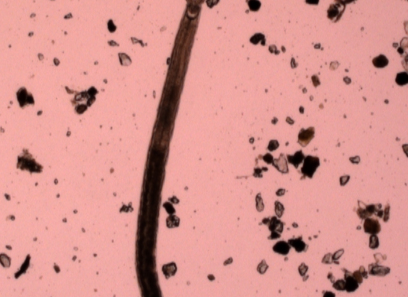

| foto_408.jpg | ![]() |